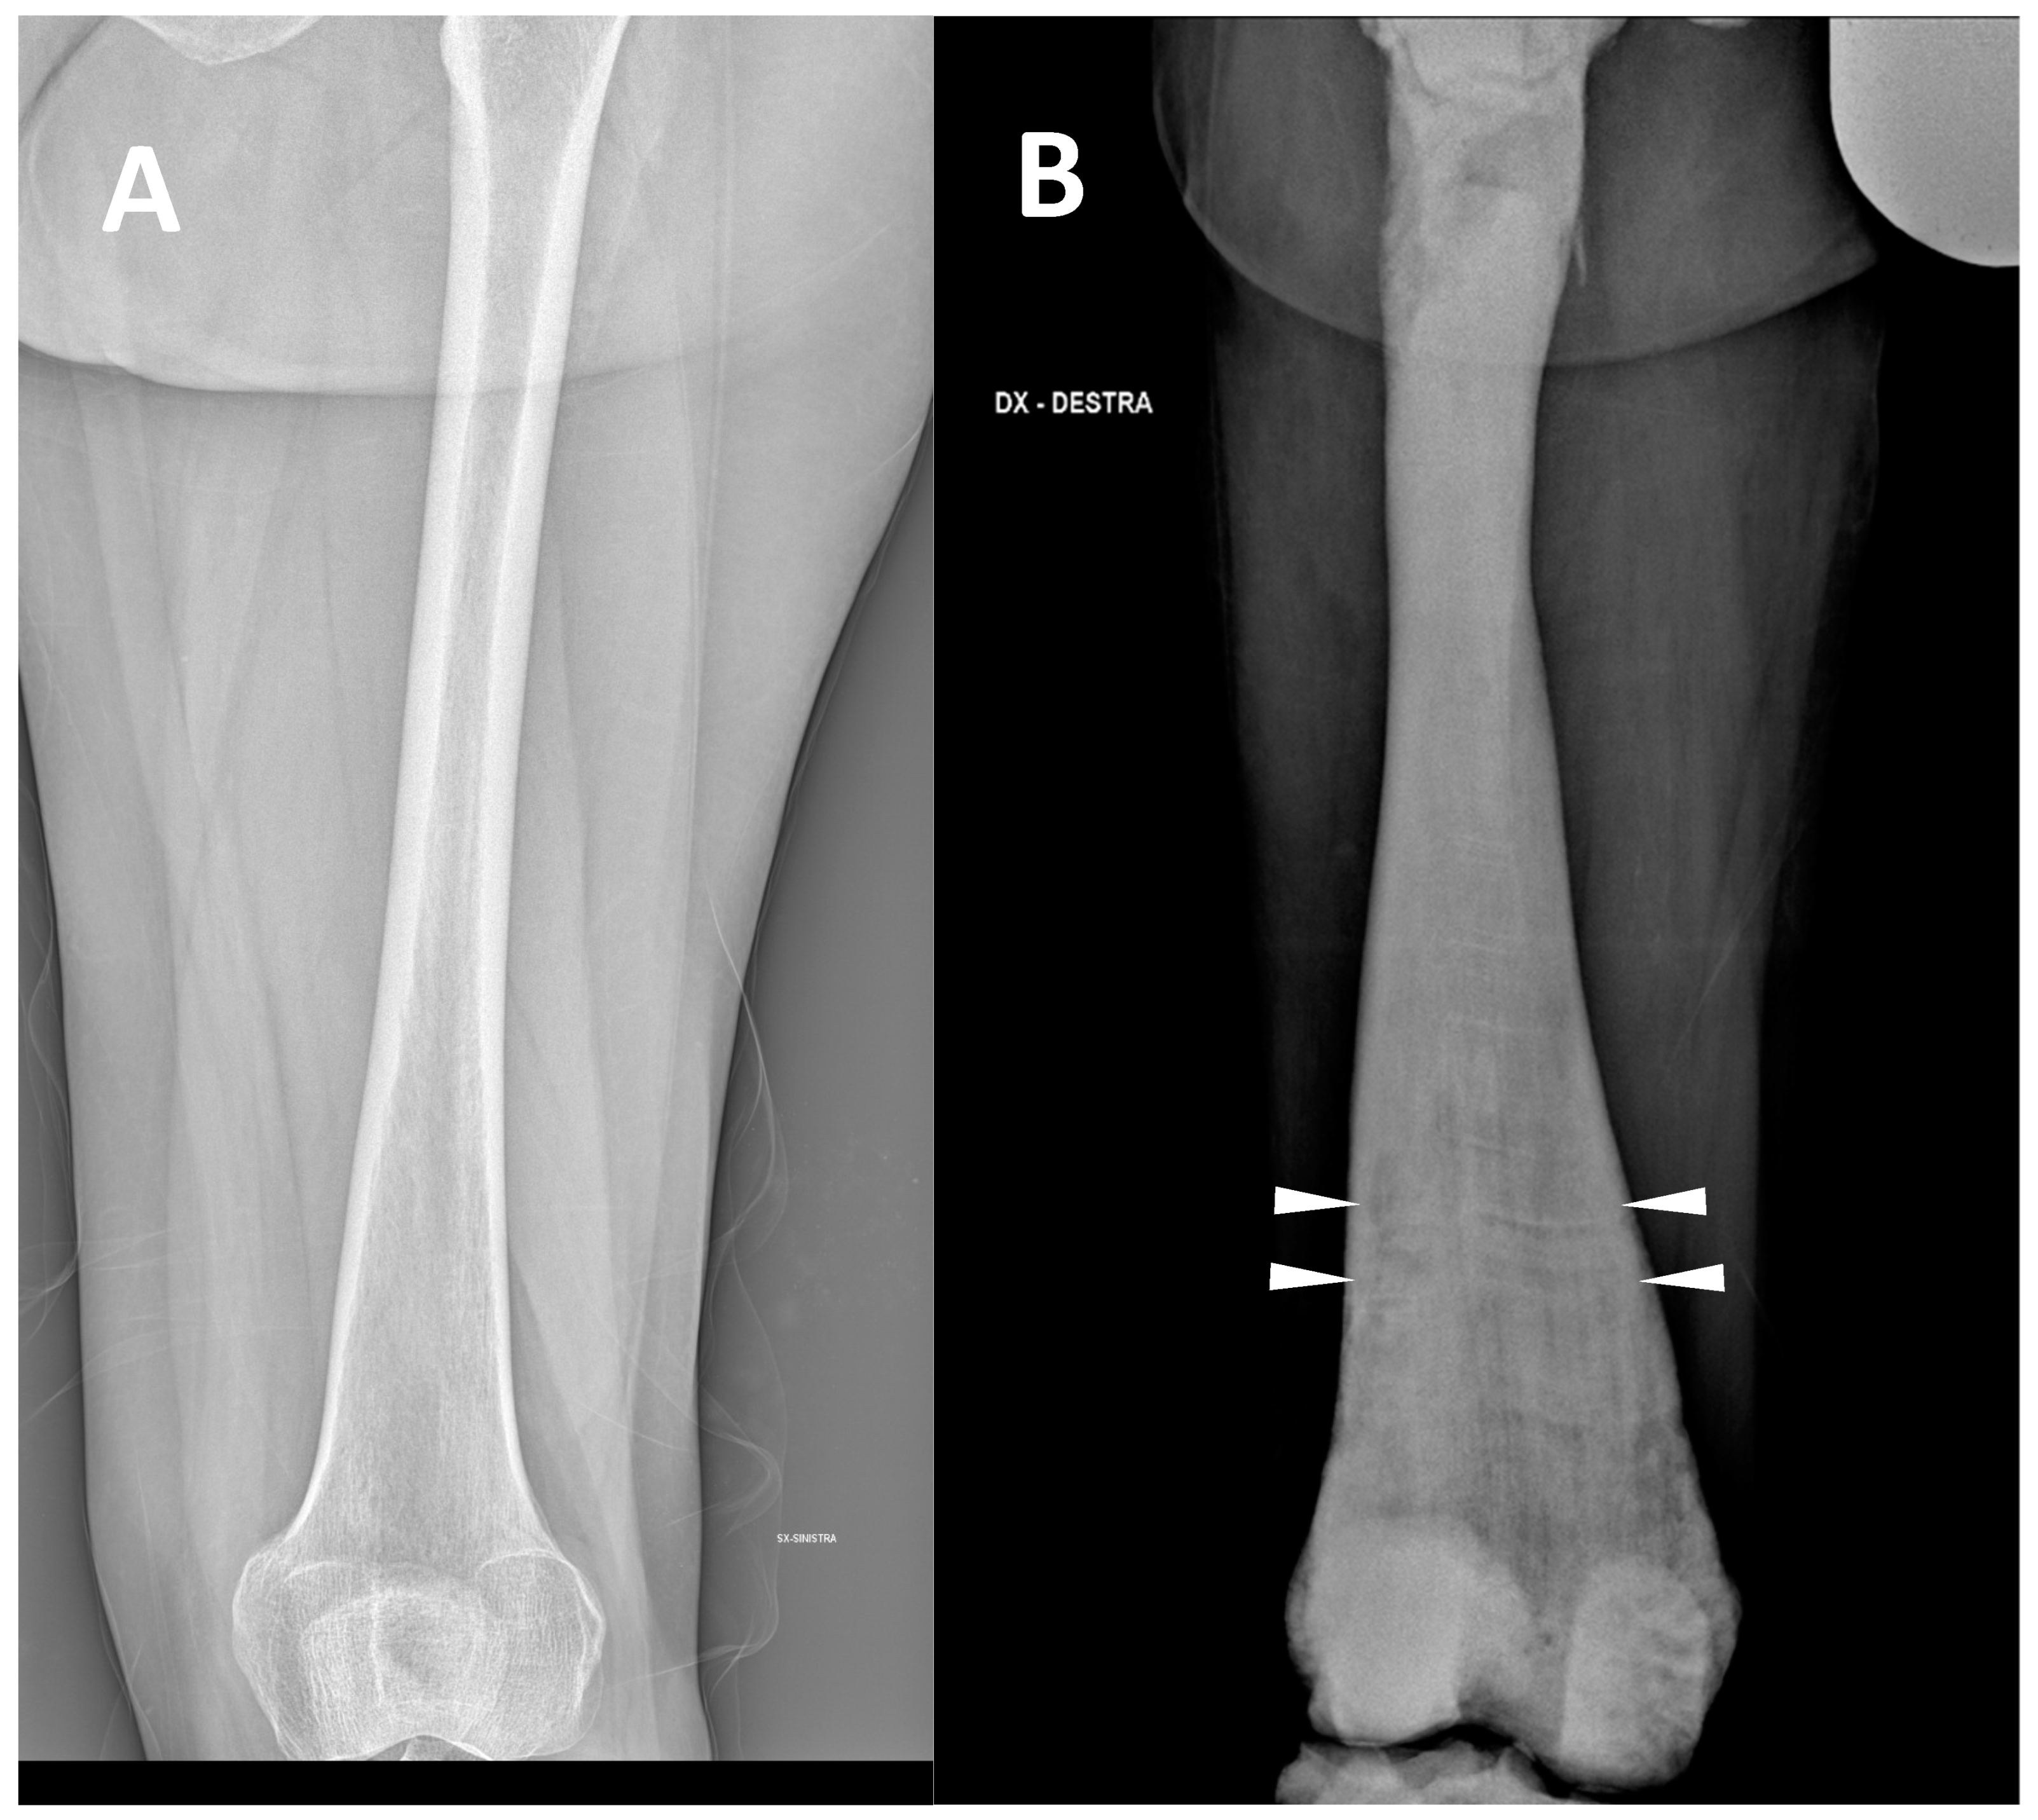

(2) Defects, enlargement/expansion, and other alterations at long bone metaphysis, which appear widened sometimes with a funnel-like shape (the so-called Erlenmeyer flask deformity) (Figure 2).

This sign consists of a lack of modelling of the dimetaphysis with abnormal cortical thinning and a lack of the concave dimetaphyseal curve [15]. This deformity results in a flask-like appearance of long bones. Indeed, this sign was firstly described in the femur, but it could be similarly found in other long bones such as the tibia and humerus. The metaphyseal enlargement/alteration leading to the ‘Erlenmeyer flask deformity’ appearance can be found in ARO, ADO type 2, and IAO osteopetrosis.

Figure 2. (A) conventional radiography of the thigh of a young healthy female (shown as comparison). (B) conventional radiography of the right thigh in a 35-year-old male affected by osteopetrosis (ARO type). Metaphyseal enlargement with the so-called ‘Erlenmeyer flask deformity’ of the distal femur, as well as a diffuse increase in bone radiolucency (increased bone density) are detectable. Alternating lucent and sclerotic metaphyseal banding can also be noted.